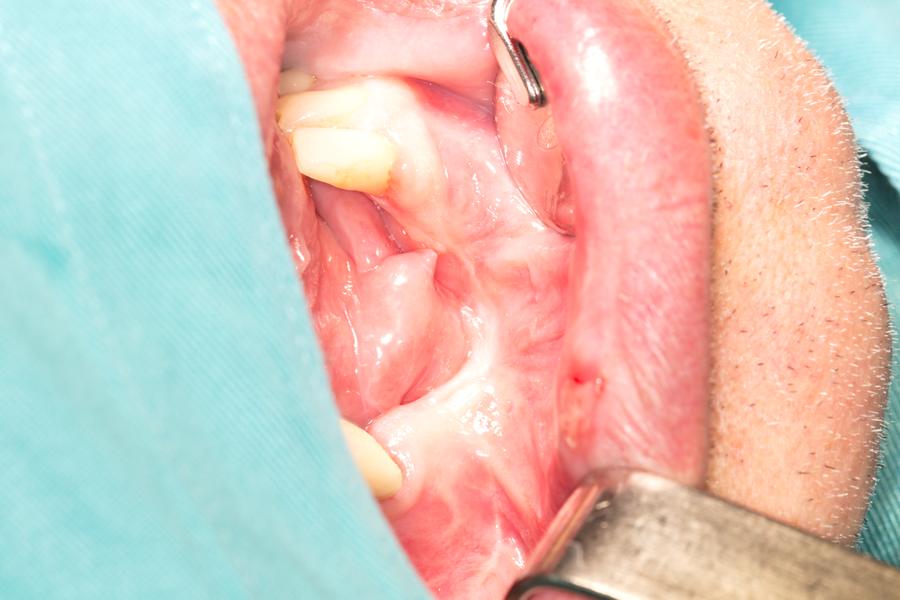

Реципиентната ложа след отпрепариране на меките тъкани. Вижда се плътна и здрава

компактна пластинка, която не е добра основа за приемане на трансплантата - тя

самата е слабо кръвоснабдена и не е добър източник на остео- и фибробласти.

Поради това е необходимо да се перфорира многократно - отворите в кортикалиса

стават източник на костни клетки и костни морфогенетични протеини, кървоносни

съдове и фибробласти, които се стремят да регенерират костта в областта на

дупчиците. Същевременно обаче те намират отлични условия за развитие около

автогенния трансплантат и водят до образуване на нова кост - поради което и

перфорациите се прилагат изключително често при необходимост от костна пластика.